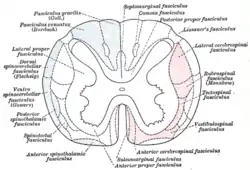

Diagram of the principal fasciculi of the spinal cord, from Gray's anatomy

Diagram of the principal fasciculi of the spinal cord, from Gray's anatomy